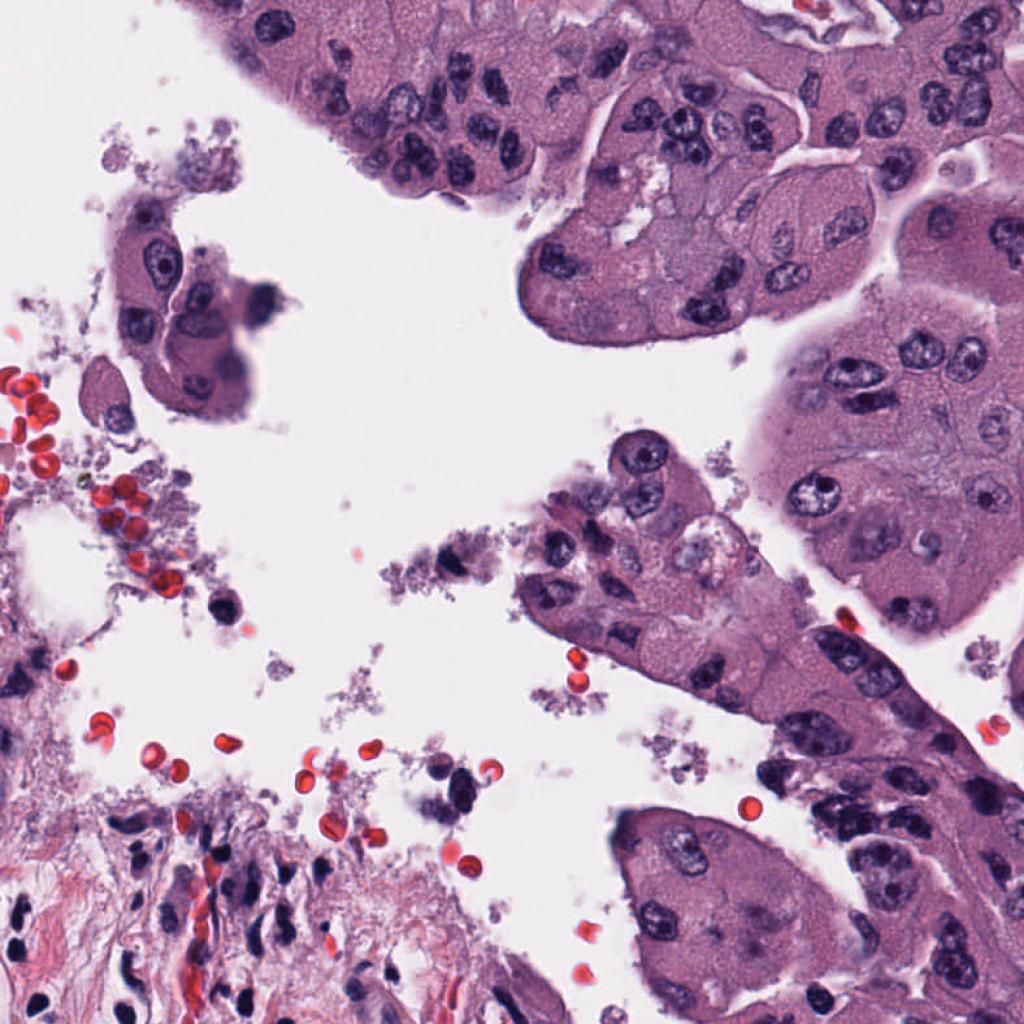

Appendix 0.A Segmentation ground truth generation with NuClick

We utilize NuClick [1], a pretrained nucleus, cell and gland segmentation model444Publicly available at https://github.com/navidstuv/NuClick, last accessed 24.11.2023, to extend the cell annotations from centroid coordinates to segmentation maps, as visualized in Figure 5. It relies on a guiding signal, in our case the cell point annotations, together with the input image for instance segmentation. Pretrained weights are only available for nuclei segmentation555https://drive.google.com/file/d/1MGjZs_-2Xo1W9NZqbq_5XLP-VbIo-ltA/view, last accessed: 24.11.2023, for this reason we extend the ground truth to a nuclei segmentation mask instead of a cell segmentation mask.